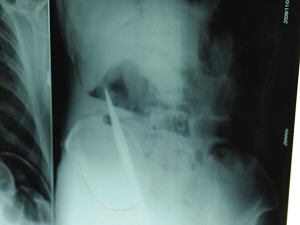

ĪĪĪĪŃ~╔Įę╗58Üq─ąūėę“Ę■ČŠ▒╗╦═ĄĮßtį║ōīŠ╚Ż¼┐╔ßt╔·▓╔╚ĪōīŠ╚┤ļ╩®║¾ģs░l¼Fą¦╣¹▓╗╝čĪŻ║¾üĒĮø╝Üų┬Öz▓ķŻ¼ßt╔·ėą┴╦éĆ¾@╚╦Ą─░l¼FŻ¼įō─ąūėĄ─¾wā╚Š╣╚╗ėąę╗░č╝ŌĄČŻ¼ßt╔·═©▀^╩ųągīó╬╗ė┌ŲõĖ╣▓┐ėęé╚ÖMĮY─cŽ┬ŠēĄ─╝ŌĄČ╚Ī┴╦│÷üĒĪŻ▀@░č╝ŌĄČūŃūŃėą19└Õ├ūķLŻĪō■ßt╔·═Ų£yŻ¼▀@░čĄČæ¬įō╩ŪÅ─ĖžķT═Ų▀M¾wā╚Ą─Ż¼▓╗ų¬─ąūė×ķ║╬Žļęį╚ń┤╦Üł┐ߥ─ĘĮ╩ĮĮY╩°ūį╝║╔·├³ĪŻė╔ė┌ōīŠ╚╝░ĢrŻ¼įō─ąūėęčĢ║Ģr├ōļx╬ŻļUĪŻ

ĪĪĪĪ6╚š╔Ž╬ńŻ¼ėøš▀į┌ąņų▌ĄVäš╝»łF┐éßtį║ųž░Y▒Oūo╩ęęŖĄĮ┴╦▀@├¹─ąūėŻ¼─┐Ū░╦¹ļm╚╗ęčĮø╗ųÅ═┴╦ęŌūRŻ¼Ą½▀Ć▓╗─▄ķ_┐┌šfįÆŻ¼ąĶę¬║¶╬³ÖC▌oų·║¶╬³ĪŻō■ßt╔·ĮķĮBŻ¼4╚šųą╬ń12Ģrū¾ėęŻ¼▀@├¹─ąūėę“Ę■ČŠ▌p╔·▒╗Šo╝▒╦═ĄĮßtį║▀MąąōīŠ╚Ż¼ų«Ū░Ż¼▀@├¹─ąūėęčĮøį┌«öĄžÓlµéßtį║▀Mąą┴╦Į³20ąĪĢrĄ─ų╬»¤Ż¼Ą½ą¦╣¹▓╗╝čĪŻĪ░▓Ī╚╦▒╗▐Dį║ĄĮĄV┐éį║Ģręč╔±ųŠ▓╗ŪÕŻ¼č¬ē║śOĄ═Ż¼╠Äė┌ą▌┐╦ĀŅæBĪŻĪ▒Š╚ūo╚╦åTĮo─ąūėŽ┤╬ĖĪó│§▓Į╠Ä└Ēęį║¾Ż¼░l¼F─ąūė║¶╬³╝▒┤┘Ż¼ė┌╩Ū┌sŠoĮo╦¹┼─Ų¼Öz▓ķĪŻĮY╣¹ūī╦∙ėąĄ─ßt╔·┤¾│įę╗¾@Ż¼Š╣ėąę╗░č╝ŌĀŅ«É╬’ÖMį┌įō─ąūėĖ╣Ū╗ā╚ŻĪ«ö╠ņŽ┬╬ń5Ģr30ĘųŻ¼▌p╔·─ąūė▒╗═Ų╔Ž┴╦╩ųąg┼_ĪŻĮø▀^40ČÓĘųńŖĄ─╩ųągŻ¼įō─ąūėĖ╣Ū╗▒╗┤“ķ_Ż¼╩ųągßt╔·░l¼FŻ¼─ąūė¾wā╚Ą─Įī┘ĀŅ«É╬’Š╣╚╗╩Ūę╗░čķL19└Õ├ūĄ─╝ŌĄČŻĪ

ĪĪĪĪßt╔·ĖµįVėøš▀Ż¼╩ųąg║¾Ż¼ßt╔·į┌▓Ī╚╦╔Ē╔Ž▓ó╬┤░l¼FĄČ║█Ż¼ūŅ║¾Ż¼Įø▀^Öz▓ķ░l¼FŻ¼į┌įō─ąūėų▒─c╠ÄšęĄĮ┤®┐ūĪŻßt╔·Å─ßtīWĮŪČ╚Ęų╬÷║¾šJ×ķŻ¼▀@░č╝ŌĄČæ¬įō╩ŪÅ─ĖžķT▓Õ╚ļų▒─cĄ─ĪŻßt╔·šfŻ¼ę“×ķ▓Ī╚╦ōīŠ╚╝░ĢrŻ¼╝ŌĄČ▓ó╬┤é¹╝░ę¬║”Ż¼╦∙ęįĢ║Ģr▒ŻūĪ┴╦ąį├³Ż¼Ą½║¾Ų┌┐╔─▄Ģ■│÷¼FĖ╣Ū╗Ėą╚ŠĪóAIDSĪóŲ„╣┘╦źĮ▀Ą╚ČÓĘN▓ó░l░YĪŻ